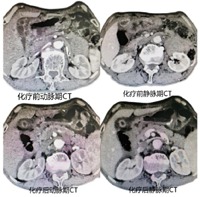

腔镜下行胃空肠吻合改流术,术后患者恢复良好,术后5 d出院。术后22 d返院行新辅助化疗,选择化疗方案为SOX,奥沙利铂130 mg/m2每21 d静脉滴注1次,同时口服替吉奥60 mg,2次/d,连续服用2周,间歇1周,连续化疗3程后,复查胃镜及全腹部CT平扫+增强,内镜下肉眼未见明显肿瘤样组织,CT提示胃窦部胃壁略增厚,与胆囊、横结肠、胰头间隙清晰,原灶区旁未见明显肿大淋巴,活检病理提示胃炎并糜烂,灶区腺体不典型增生。综合考虑肿瘤经新辅助化疗后完全退缩(TRG分级0级,图1,图2,图3,图4)。于9月29日在全麻下行腹腔镜下远端胃癌根治术,拆除原吻合口,行腹腔镜下远端胃D2清扫,近端残胃与空肠吻合,再行近端空肠与距离胃肠吻合口约40 cm空肠吻合,术中发现原腹腔镜探查肿瘤侵犯胆囊、横结肠、横结肠系膜、胰头十二指肠韧带间隙清晰,切取粘连组织术中冰冻均未发现癌细胞,手术选择未联合脏器切除。

此病例在新辅助化疗前诊断(腺癌cT4bN+M0),根据中国抗癌协会胃癌专业委员会发布的《局部进展期胃癌围手术期治疗中国专家共识》(2021版)[1]推荐新辅助化疗或联合放疗,4程新辅助治疗后复查等待肿瘤降期或退缩后抓住时间窗再行根治手术治疗。首次住院完善检查评估经过MDT讨论后考虑肿瘤分型为BorrmannⅢ型,需先行新辅助化疗,但患者有幽门梗阻症状,决定先行腹腔镜探查及全腔镜下胃空肠吻合改流手术,同时也是遵循对于BorrmannⅢ型、大于8 cm的肿瘤建议行腹腔镜探查了解腹膜、网膜、系膜是否存在转移,获得腹腔镜探查肿瘤分期及可切除性评估,探查证实肿瘤位于胃窦部环周,6 cm×8 cm大小,侵出浆膜,侵犯胆囊、横结肠、十二指肠韧带、胰头和横结肠系膜,灶区旁多发淋巴结肿大,肝、脾、腹膜未见转移及种植癌结节。初步判断为不可切除局部进展期胃癌,术后给予SOX方案行新辅助化疗[2],经过三程新辅助化疗后复查胃镜前后对比,内镜下发现肿瘤完全退缩,活检病理同样支持病理完全退缩(图1、图2),复查全腹部CT+增强扫描可以了解原灶区明显降期,胃窦部胃壁稍增厚,与胆囊、横结肠、胰腺的界限清晰,灶区周围未见明显肿大淋巴结(图3),从影像学角度分析肿瘤退缩明显,转化至可切除范畴。指南推荐术前新辅助化疗4程到6程后评估效果,此病例在术前新辅助化疗3程后全面评估后无论从影像学及内镜检查还是病理学上均获得良好退缩改变,在术前新辅助化疗期间注意观察患者血红蛋白、白细胞、血小板及癌胚抗原,随着化疗的进行患者还是出现了轻度骨髓抑制,白细胞、血红蛋白均有不同程度的下降[3],血小板仍在正常范围内,暂不制约新辅助化疗的进行,但随访癌胚抗原的结果在第1次、第2次新辅助化疗时虽较前均有升高,但仍在正常范围内,且升高幅度均低于30%,而第3次化疗时复查癌胚抗原高于正常值,且升高幅度大于60%(图4),在影像学、内镜及病理检查均获得完全退缩情况下[4],CEA反而升高,此时我们认为新辅助化疗的再评估时间不是机械的固定在4~6个疗程,需综合参考血红蛋白、白细胞、血小板变化情况,特别需要关注CEA的变化情况[5],在新辅助化疗可能出现耐药或者可能出现复发转移的时间窗口及时评估肿瘤退缩评分,及时评估肿瘤的可切除或不可切除性,积极引入外科手术干预,不至于错过最好的手术时机[6]。